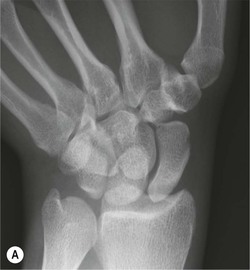

The scapholunate ligament is most frequently involved. Radiographs may show scapholunate diastasis (>3 mm). The lunate demonstrates dorsal rotation on lateral views and volar rotation of the scaphoid. This results in an increase in the scapholunate angle (>60°) known as dorsal intercalated segment instability (DISI) (Fig. 46-27). A DISI deformity of the carpus may also be associated with fractures of the scaphoid.

More subtle degrees of instability may be demonstrated by an instability series of radiographs acquired with radial and ulnar deviation and with a clenched fist view. Video fluoroscopy is also useful for assessing dynamic wrist instability.